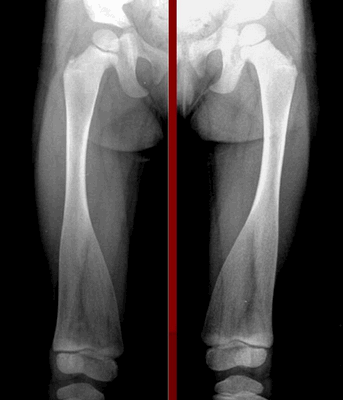

Заболевание сложно обнаружить без рентгенологического исследования. Среди характерных признаков - конусообразное расширение в трубчатых костях нижних конечностей. Они по форме начинают напоминать стеклянные колбы, используемые в лабораториях.

Симптомы метафизарной дисплазии

Характерным признаком заболевания является сильное смещение трубчатых костей при одновременном и значительном расширении колбы Эрленмейера в ногах. Особенно симптомы выражены при поражении бедренной части. При метафизарной дисплазии негативные изменения в строении черепа минимальны. В редких случаях сильно выступают лобные доли над глазницами, создавая асимметричное строение лица.

При диагностике врачи обращают внимание на характерное поражение проксимального отдела шейки бедра. Кости имеют неправильную форму, недостаточную плотность, низкое содержание кальция и микроэлементов. На рентгеновских снимках заметны неровные контуры, расширенные участки эпифизов.

Для пациентов с типом MакКьюзика характерны хроническая анемия, патологии кишечника. На рентгеновских снимках заметно увеличение метафизов в области коленного сустава. В детском возрасте нередко встречается двояковыпуклое строение позвонков, которое постепенно исчезает после взросления.